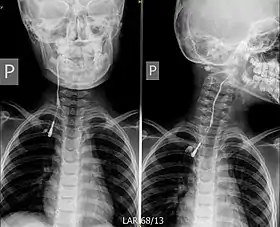

La TC y la punción-aspiración con aguja fina (PAAF) son las exploraciones complementarias más útiles. En aquellos supuestos en los que exista una fístula externa, la realización de una fistulografía con contraste resultará conveniente para mostrar el recorrido fistuloso.[6]